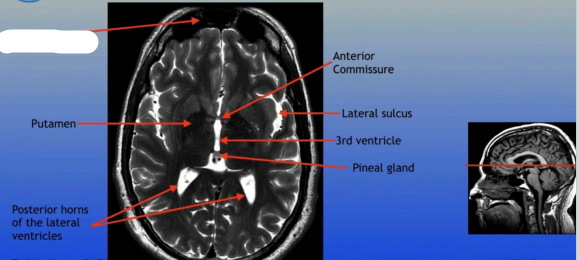

Putamen

Posterior Horns of the Lateral Ventricles

Anterior Commissure